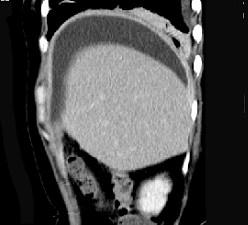

问题 女,59岁,发热、右上腹痛、右下肺呼吸音低,影像检查如图,最可能诊断是 ( )

选项 A、肝硬化腹水 B、大网膜膈下间位 C、膈下脓肿 D、肝包膜下出血 E、腹腔积液

答案 C